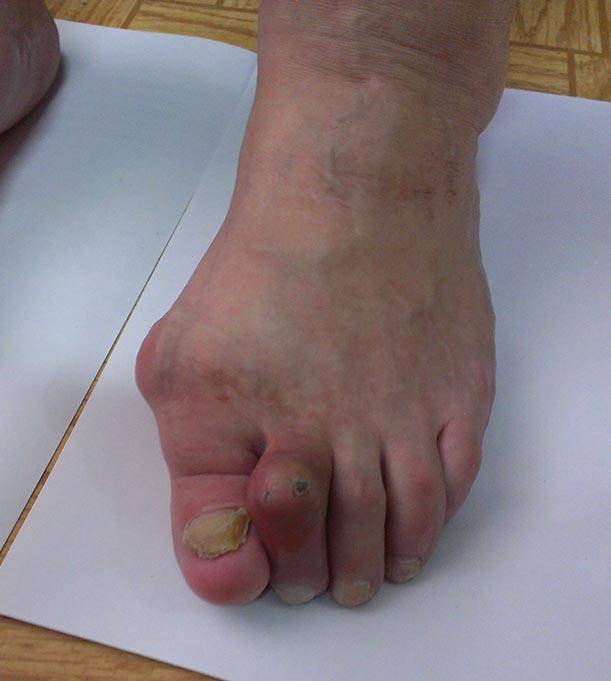

Женщина 60 лет,имеет деформацию пеереднего отдела обеих стоп в виде

Hallux valgus, молоткообразной деформации вторых пальцев, артроза первых

плюсне-фаланговых и других суставов. Каков может быть объем коррекции

стоп, с учетом артроза слева?